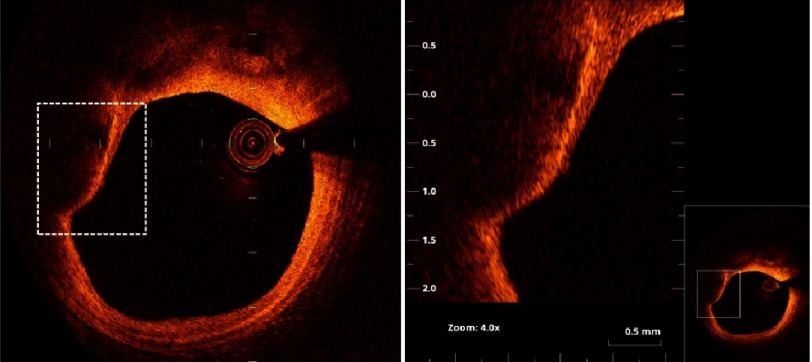

Figure 10. Thin cap fibro-atheroma.

The right panel is magnification of the square in the left panel (as shown in thumbnail). A plaque with large ill-defined lipid pool and thin fibrous cap (measuring 58 µm). The arrow points to accumulation of macrophages (the bright line) beneath the thin cap.